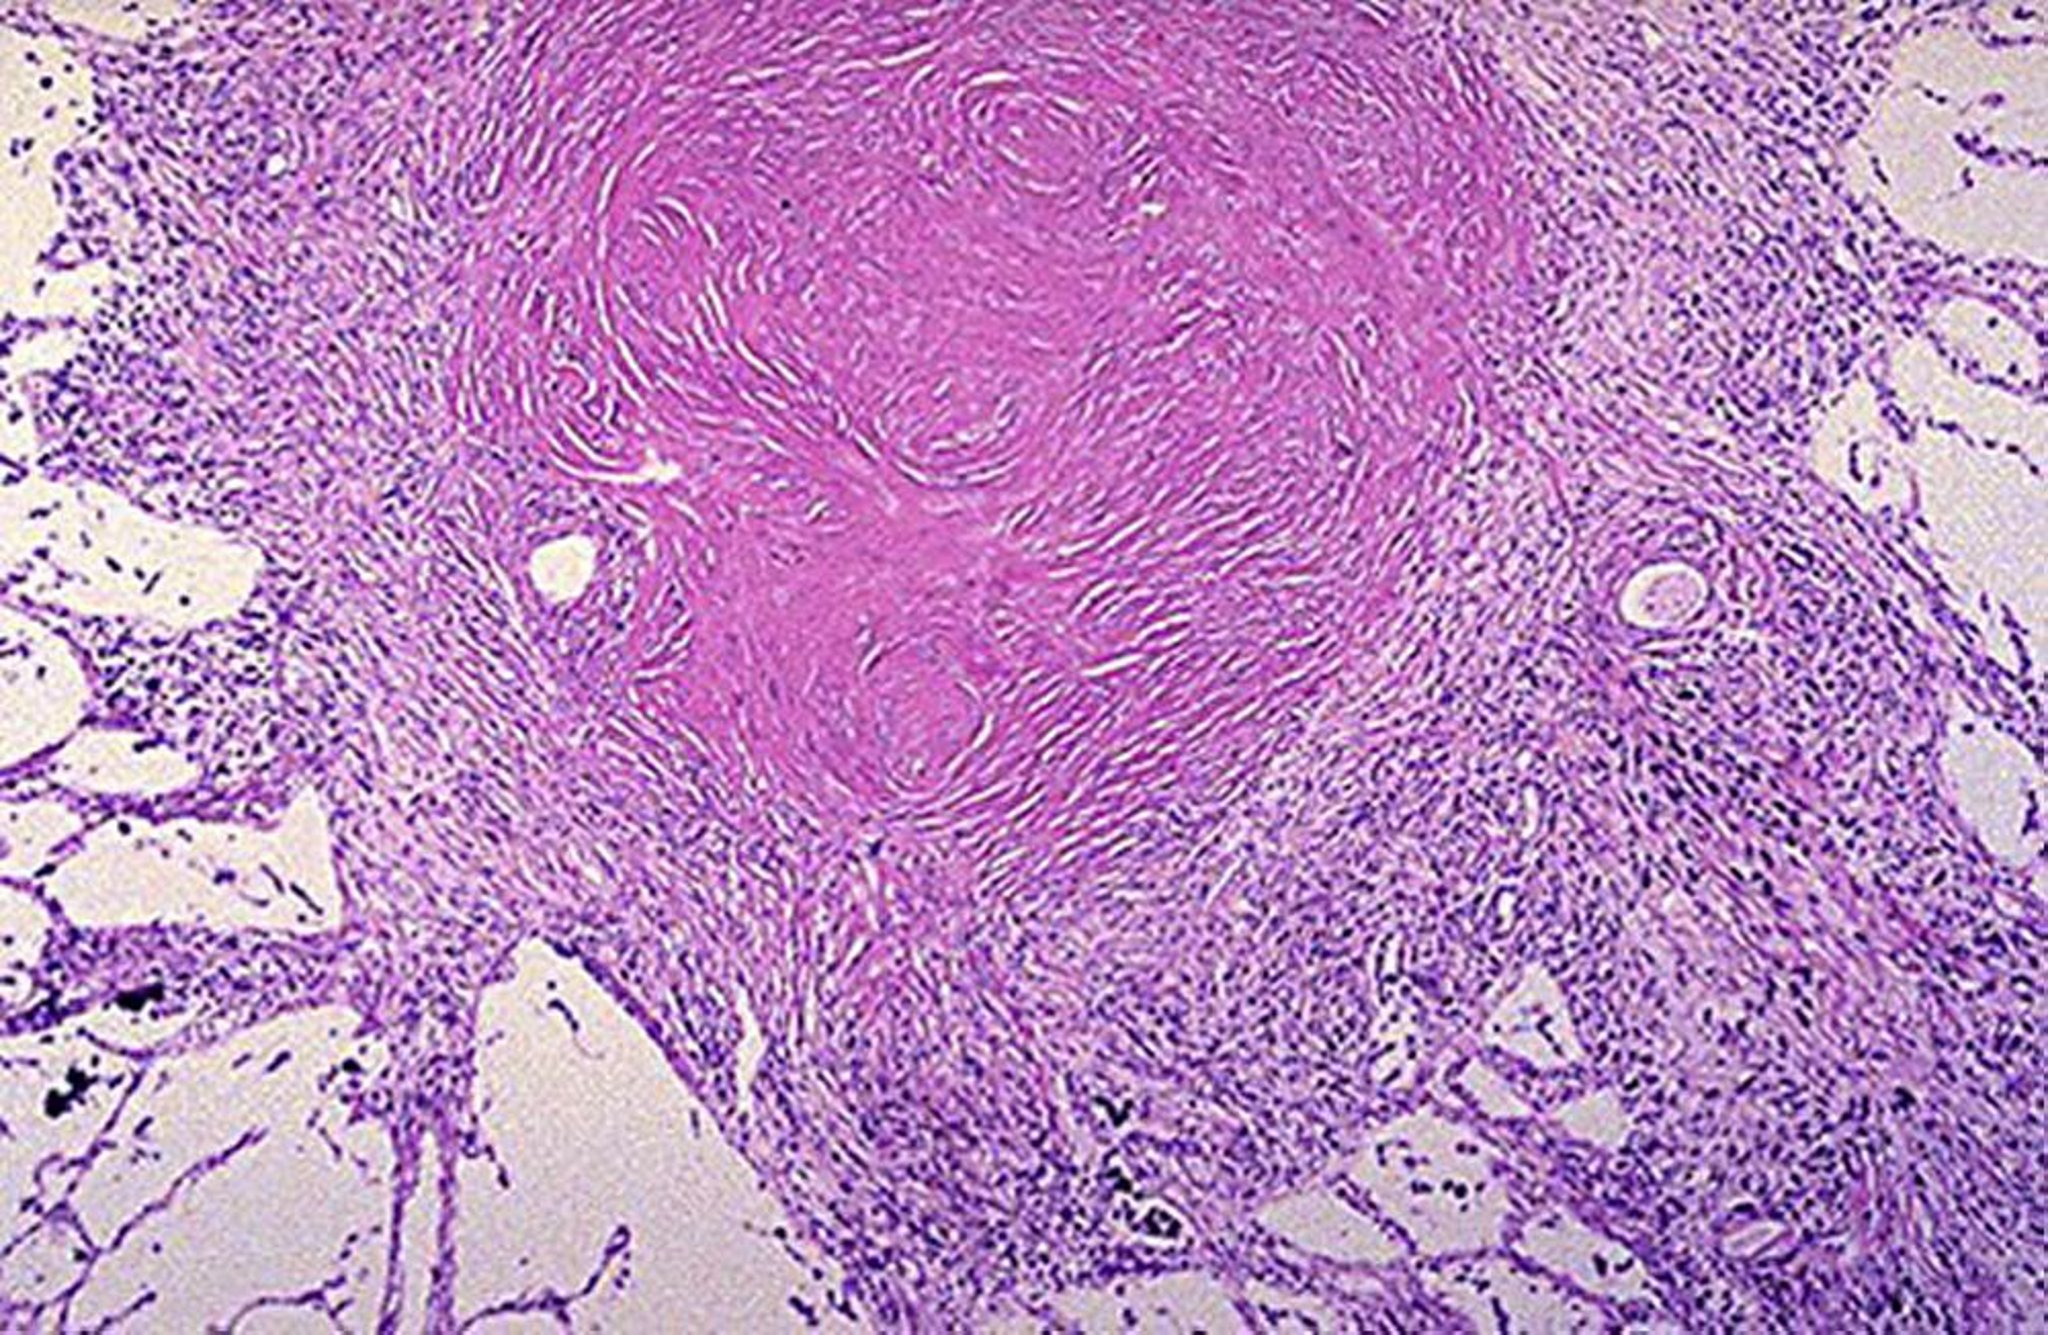

Nódulo silicótico

Imagem cedida por cortesia de David W. Cugell, MD.

• Silicose >